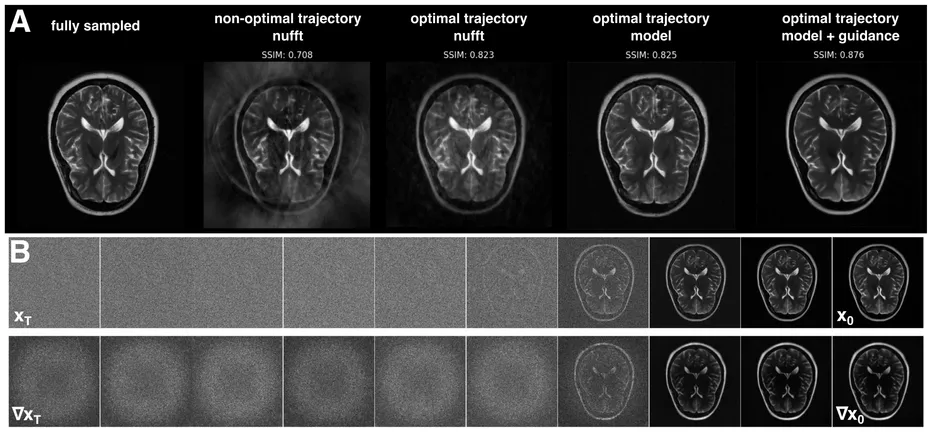

11 MRI Reconstruction